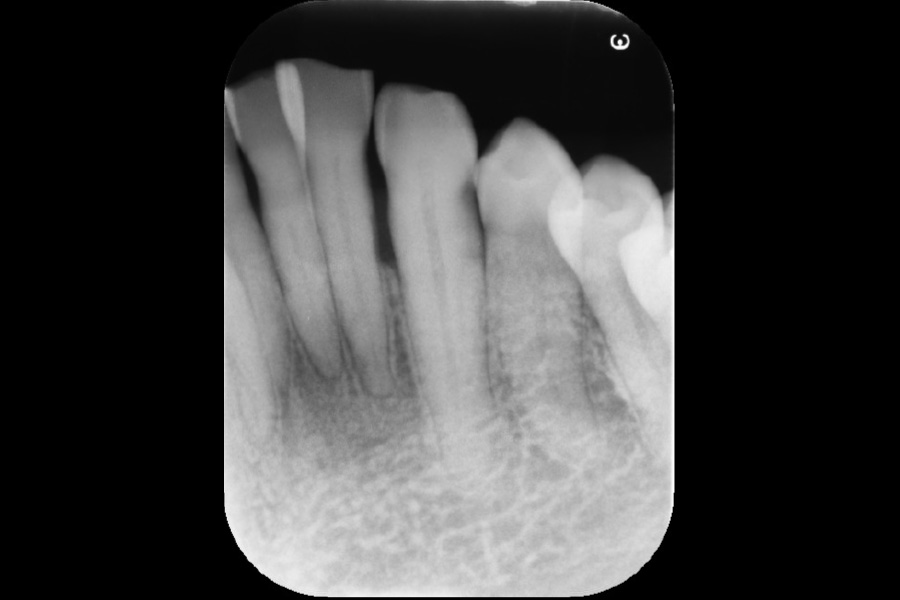

下の前歯から出血する

【歯周組織再生療法】

- 主訴

- 下の前歯から出血する

- 治療内容

- 左下2遠心に垂直性骨吸収が認められたためエムドゲインと骨補填材を用いて歯周組織再生療法を行った